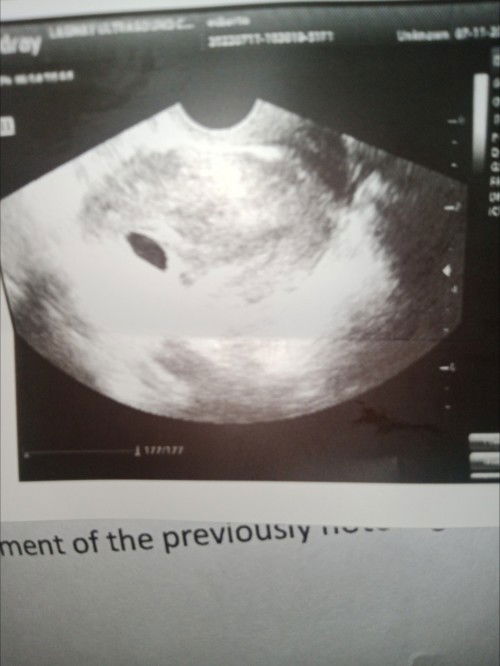

Mga sis sino nakaranas dto ng blighted ovum daw sa 6 weeks and 5 days

Nagpa transvaginal aku kahapon ang sabi ng ng ultrasound blighted ovum daw bugok na buntis hindi po aku nakampanti inulit ku ulit mag pa transvaginal ultrasound sa ibang clinic and ang sabi baka maaga pa daw balik aku after two weeks kung d naman daw aku dinugudo. Mga sis anu pwedi kung gawin. #advicepls #1stimemom #pregnancy #pleasehelp #firstbaby #firstmom